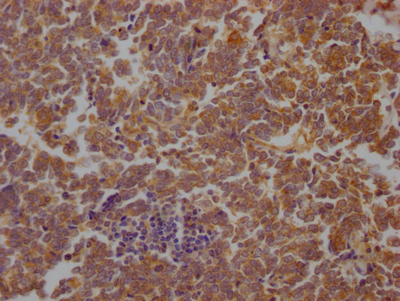

• IHC image of CSB-RA229700A0HU diluted at 1:100 and staining in paraffin-embedded human lung cancer performed on a Leica BondTM system. After dewaxing and hydration, antigen retrieval was mediated by high pressure in a citrate buffer (pH 6.0). Section was blocked with 10% normal goat serum 30min at RT. Then primary antibody (1% BSA) was incubated at 4℃ overnight. The primary is detected by a Goat anti-rabbit IgG polymer labeled by HRP and visualized using 0.05% DAB.